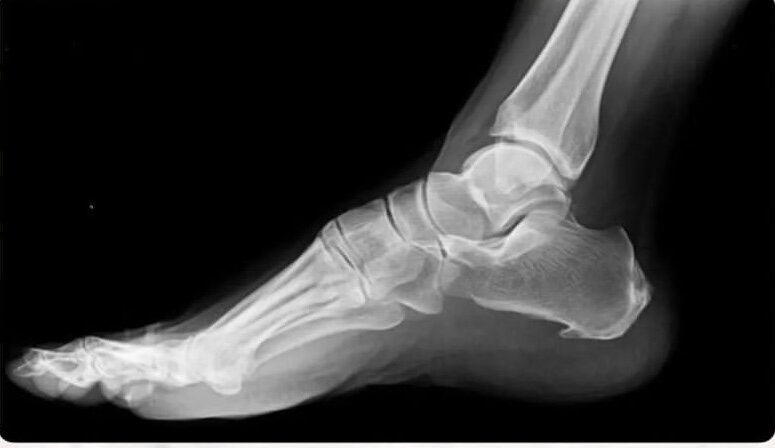

Продольные краевые микро надрывы заполняются плотными элементами, поэтому на рентгене в боковой проекции мы наблюдаем некий вырост из пяточ

Продольные краевые микро надрывы заполняются плотными элементами, поэтому на рентгене в боковой проекции мы наблюдаем некий вырост из пяточной кости, визуально напоминающий шпору на ноге петуха.

Диагностируют ПФ исходя из жалоб клиента (симптом первого шага), пальпации подошвы, УЗИ или рентгенографии стопы в боковой проекции.